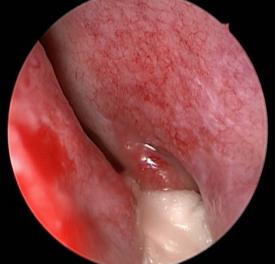

鼻腔內淚囊的位置(黃色標記)